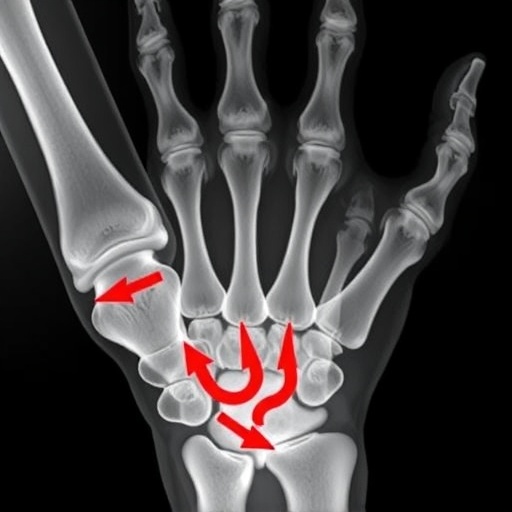

Malunited distal radius fractures, which occur when a fracture does not heal correctly, are a common affliction in orthopedic medicine. Such fractures often lead to long-term complications, including chronic pain, loss of function, and reduced quality of life. Standard treatment for malunited fractures often involves corrective osteotomy—a surgical procedure aimed at realigning the bone. However, the success of this surgery heavily relies on precise planning and execution, which are made all the more complex due to the intricate anatomy of the wrist. Here is where augmented reality steps in as a game changer.

The research team conducted a series of experiments to assess the effectiveness of the AR-assisted osteotomy guide in human subjects. In a meticulously controlled environment, the researchers made use of 3D imaging technology to construct virtual models of the distal radius of patients suffering from malunited fractures. These models were then programmed to interactively guide the surgeons through the osteotomy procedures by projecting the anatomical dimensions and angles onto the actual surgical field. The early results of these experiments show promise, suggesting that surgeons experienced a significant improvement in the accuracy of their cuts and realignments.